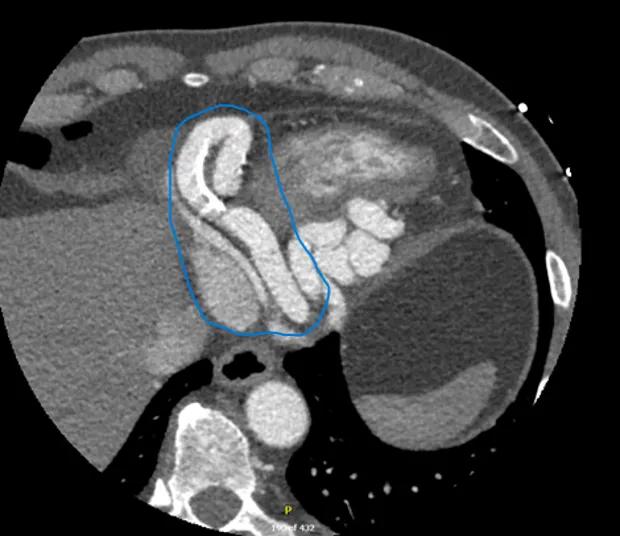

The patient was evaluated by cardiologist Nicholas Ruthmann, MD, and cardiothoracic surgeon Faisal Bakaeen, MD. They found him to be an active individual with mild shortness of breath and fatigue on exertion. A review of his coronary CT scans confirmed a right CAA 1.5 cm in diameter (Figure 1). Nuclear imaging tests revealed mild ischemia in the right ventricle. Their concern was that the patient’s right ventricular function would be severely affected over time due to an increase in loading conditions caused by the fistula.

CAT scan of a heart with a blue circled area

Figure 1. The patient’s CT showing the right coronary artery aneurysm within the blue tracing.